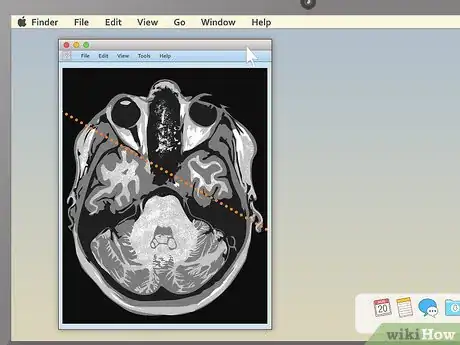

4Use the section-cut line to see where cross-sections are located. If you display a cross-sectional image along with a sagittal or coronal image, you may see a section-cut line on the second image. This will be a straight line running through the image, but it may not be present on all MRIs. If your image does have one, this shows where on the second image the cross section is located. You should be able to move the section cut line toward the center, right or left of the image. This will change the larger layout image to show the body from the new direction of the scan.

- The section-cut line on the layout picture also shows the direction that the image was taken from. For example, if your MRI were a picture of an everyday object, like a tree, the section cut line might show you if the picture was taken from above in a plane, from a second-story window, or from the ground.

5Drag the section-cut line to view new parts of the study. Dragging the section-cut line to a different part of the image allows you to "move around" your MRI images. The image should change your view to the new area automatically.

- For example, if you're viewing a sagittal image of your spine along with a cross section of one of your vertebrae, moving the section-cut line may allow you to cycle up and down through the various vertebrae above and below it. This can be useful for locating problems like herniated discs.